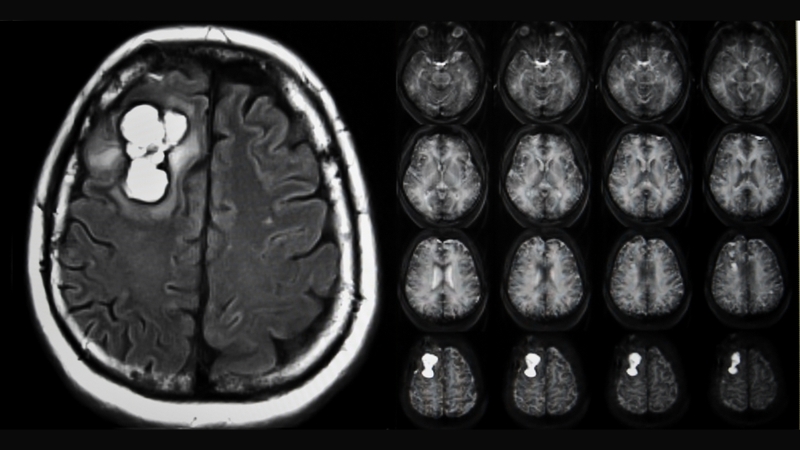

Áp lực nội sọ bình thường khoảng 7 – 15 mmHg. Nếu tăng lớn hơn 20 mgHg được gọi là tăng áp lực nội sọ. Tăng áp lực nội sọ là một trường hợp khẩn cấp đe dọa tính mạng và cần được chăm sóc y tế ngay lập tức để ngăn ngừa tổn thương vĩnh viễn hoặc tử vong.

Áp lực nội sọ (ICP) là áp lực gây ra bởi dịch não tủy, mô não và máu bên trong hộp sọ. Thể tích não chiếm 80%, máu 10% và dịch não tủy chiếm 10% trong hộp sọ. Áp lực nội sọ được đo bằng milimet thủy ngân (mmHg), thường là 7-15 mmHg.

Tăng huyết áp nội sọ khi áp lực lực nội sọ ở mức lớn hơn 20 mmHg. Để hiểu rõ về tăng áp lực nội sọ, hãy nghĩ hộp sọ như một cái hộp cứng. Sau chấn thương não, hộp sọ có thể bị lấp đầy bởi mô não, máu hoặc dịch não tủy. Hộp sọ sẽ không căng ra như da để đối phó với những thay đổi này. Hộp sọ có thể trở nên quá đầy và làm tăng áp lực lên mô não. Điều này được gọi là tăng áp lực nội sọ.

Tăng áp lực nội sọ thường gặp trong các tình huống chấn thương sọ não, u não,… Tuy nhiên cũng có nhiều trường hợp có thể không tìm ra nguyên nhân, còn được gọi là tăng áp lực nội sọ vô căn, những người có nguy cơ mắc tăng áp lực nội sọ vô căn thường là phụ nữ 20-50 tuổi, béo phì, hội chứng Cushing, suy giáp hoặc cường giáp. Áp lực nội sọ tăng kéo dài trong tăng áp nội sọ vô căn có thể dẫn đến mất thị lực vĩnh viễn.

Khi xuất hiện triệu chứng đau đầu và nhìn mờ mà không rõ nguyên nhân, cần thực hiện chụp cắt lớp sọ não để loại trừ khả năng tăng áp lực nội sọ. Khi xác định tăng áp lực nội sọ, bệnh nhân phải được theo dõi chặt chẽ và xử lý nguyên nhân gây ra tình trạng này một cách kịp thời.